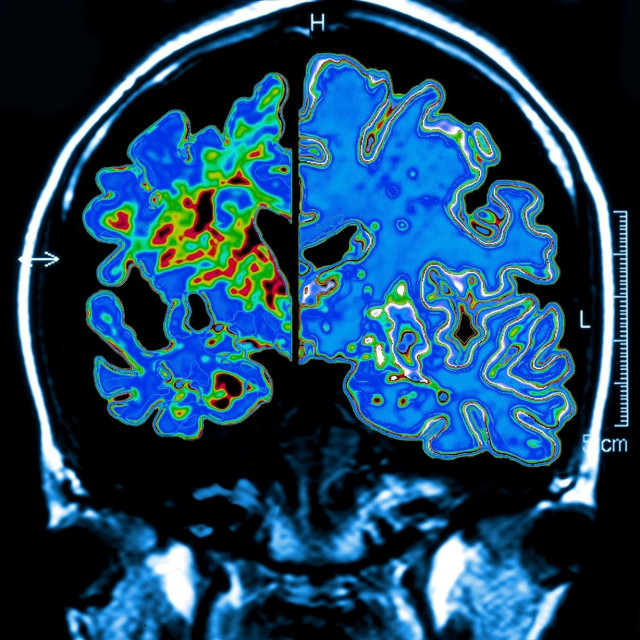

Alzheimerova bolest, Ilustracija

Pasieka/Sciencephoto/Profimedia

Ovo je ujedno prvi lijek koji je usmjeren na uzrok bolesti, "prisutnost beta-amiloidnog plaka u mozgu", a ne samo na simptome koje ona uzrokuje, dodala je.